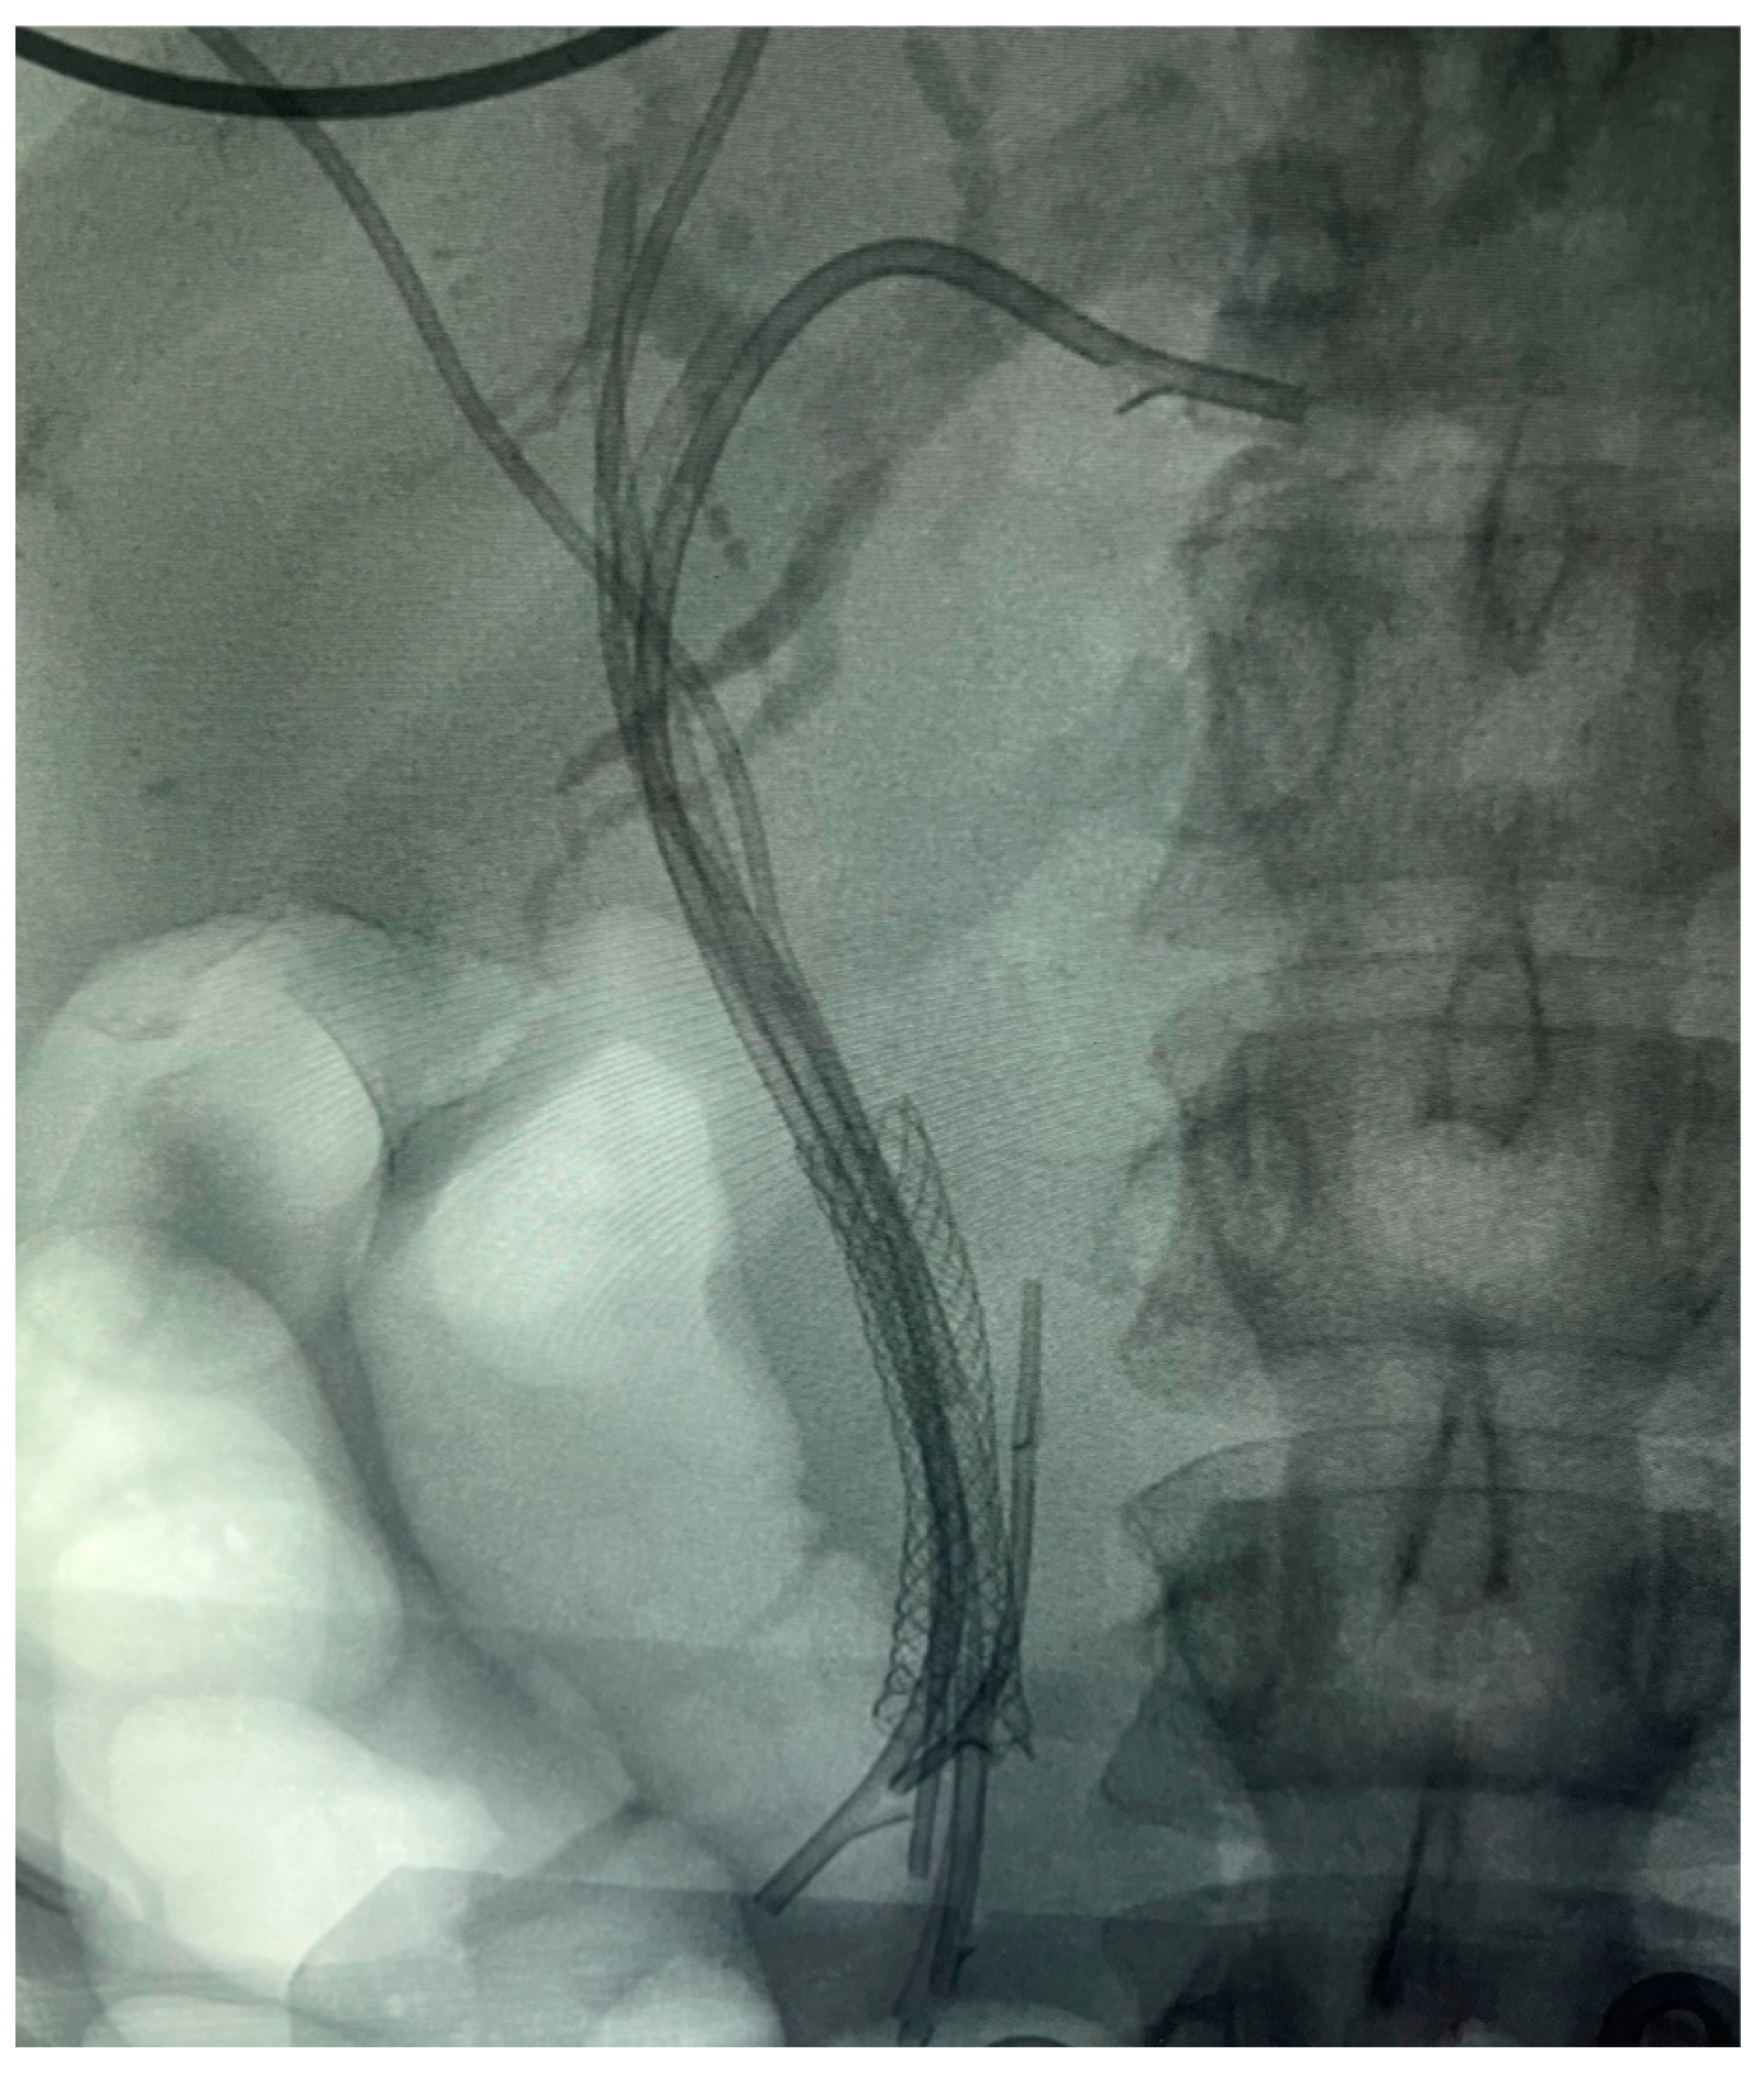

7.1.1. Endoscopic Biliary Stenting (EBS)

- Kawashima, H.; Ohno, E.; Ishikawa, T.; Mizutani, Y.; Iida, T.; Yamamura, T.; Kakushima, N.; Furukawa, K.; Nakamura, M. Endoscopic management of perihilar cholangiocarcinoma. Dig. Endosc. 2022, 34, 1147–1156. [Google Scholar] [CrossRef]

- Naitoh, I.; Ohara, H.; Nakazawa, T.; Ando, T.; Hayashi, K.; Okumura, F.; Okayama, Y.; Sano, H.; Kitajima, Y.; Hirai, M.; et al. Unilateral versus bilateral endoscopic metal stenting for malignant hilar biliary obstruction. J. Gastroenterol. Hepatol. 2009, 24, 552–557. [Google Scholar] [CrossRef] [PubMed]

- Lee, T.H.; Moon, J.H.; Choi, J.H.; Lee, S.H.; Lee, Y.N.; Paik, W.H.; Jang, D.K.; Cho, B.W.; Yang, J.K.; Hwangbo, Y.; et al. Prospective comparison of endoscopic bilateral stent-in-stent versus stent-by-stent deployment for inoperable advanced malignant hilar biliary stricture. Gastrointest. Endosc. 2019, 90, 222–230. [Google Scholar] [CrossRef] [PubMed]